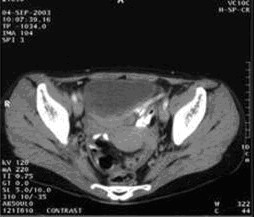

女,49歲。胃體癌晚期,胃竇增厚強(qiáng)化,與周?chē)尺B,腹膜增厚,腹腔廣泛轉(zhuǎn)移,伴大量腹水。放/化療失敗,無(wú)法手術(shù)。治療方案:腹腔灌注今又生2×1012VP/2次/周,共12周,同時(shí)灌注順鉑和5-氟尿嘧啶腹腔,后4周加8次全腹熱療。治療后:第3周,腹水消失;第8周,胃竇、腹膜和網(wǎng)膜變薄,盆腔結(jié)節(jié)明顯變小。后行手術(shù)切除殘余胃腫瘤,術(shù)中探查全腹和盆腔未捫及腫瘤。術(shù)后病檢胃腫瘤內(nèi)未見(jiàn)癌細(xì)胞。

盆腔